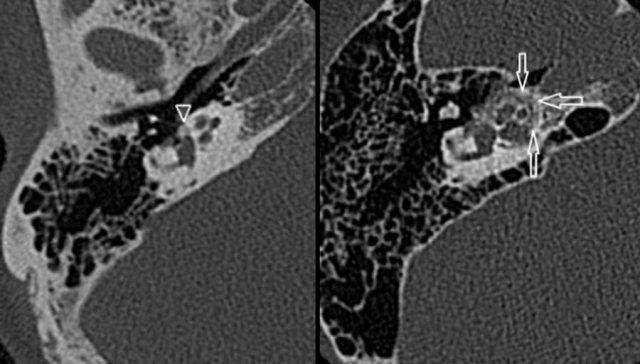

Xơ cứng tai: xương giảm tỷ trọng ở vùng fissula ante fenestram trong xơ cứng tai thể cửa sổ (trái). Xơ cứng tai thể ốc tai biểu hiện là một vùng hào quang giảm tỷ trọng bao quanh ốc tai trên CT (phải).

CT độ phân giải cao, lát mỏng thường cho thấy xương giảm tỷ trọng bất thường ở vùng fissula ante fenestram trong xơ cứng tai thể cửa sổ (trái).

Xơ cứng tai thể ốc tai

Biểu hiện là một vùng hào quang giảm tỷ trọng bao quanh ốc tai trên CT (phải).

CT trục bên trái cho thấy khối mô mềm ở tai giữa (mũi tên).

Không thấy tiêu xương rõ ràng.

MRI chuỗi xung T1W có tiêm thuốc tương phản từ kết hợp xóa mỡ trục bên phải cho thấy tổn thương ngấm thuốc mạnh (đầu mũi tên).